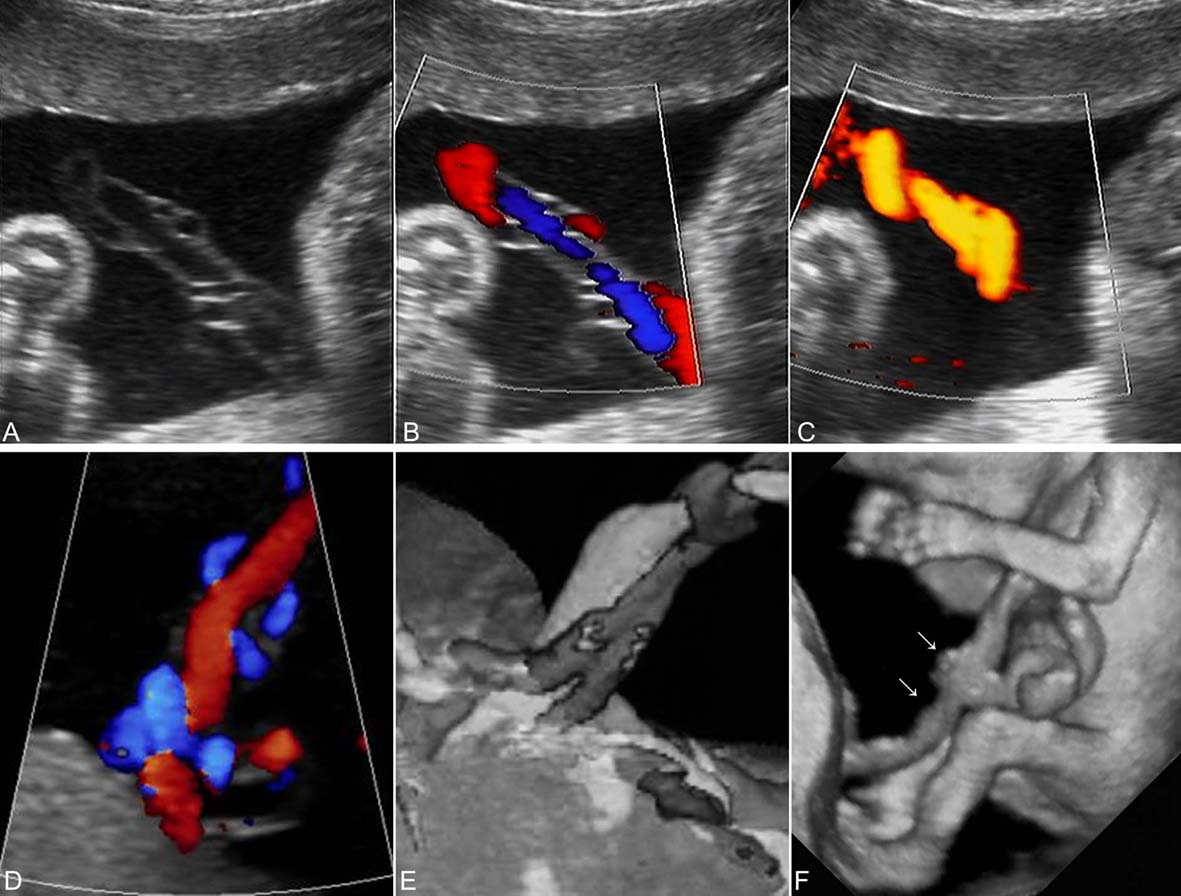

典型的脐带回声要在妊娠14~16孕周以后显示。超声显像检查在羊水无回声区内显示脐带回声,在分辨力良好的情况下,可以显示脐带内的两条动脉和一条静脉。脐动脉较细,脐静脉较粗,二者比值为1:1.5~2;脐静脉在妊娠30周时内径可达到最大的9mm,三者绞合呈绳索状漂浮在羊水无回声区内(图4A);使用CDFI检查及能量图检查可以清晰显示脐带内的血流(图4B、C、D);三维超声显像检查可以形象地显示脐带结构(图4E、F)。不同孕龄的胎儿脐动脉血流速度曲线有明显的不同(图5)。

图4脐带超声检查显示